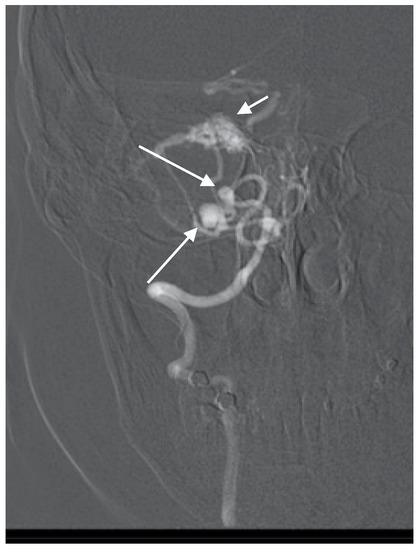

A 60-year-old woman was admitted for abrupt loss of consciousness. CT in a peripheral setting showed cerebellar hemorrhage with a pan-intraventricular hematoma in the fourth ventricle and a massive SAH in the cerebellar and spinal canal regions (Figure 4). AG revealed three aneurysms on the distal PICA (Figure 5), successfully excluded from circulation by microsurgery clipping while maintaining patency of the PICA. During the surgery, sudden intraoperative rupture occurred from the most peripheral aneurysm, located just under the arachnoid membrane on the surface of the cerebellum. After easy clipping of the neck, the feeding vessel was followed in the hematoma to its telovelotonsillar part, where another two aneurysms were visible. With the technique of temporary clipping, the optimal final position on both clips was achieved in the wide necked aneurysms. The patency was confirmed with intraoperative ultrasound. A difficult postoperative course and hydrocephalus required temporary ventricular drainage, which was converted to a ventriculo peritoneal (VP) shunt with a good long-term result.

Figure 5. Oblique projection of an angiogram with three PICA aneurysms.